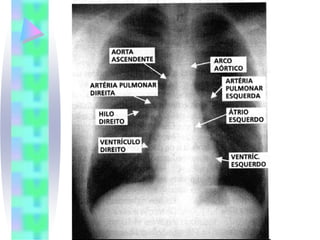

Radiologia

• Problemas que podem ser sugeridos ou

diagnosticados pelo RX de tórax

•   ICC

•   Edema Pulmonar

•   Derrame Pleural

•   Hipertensão Pulmonar Severa

•   Malformações Congênitas

•   Shunt esquerda-direita

•   Doença Cardíaca Valvar

•   Pericardite construtiva calcificada

•   Grandes Derrames Pericárdicos

•   Cisto pericárdico

•   Miocardiopatia

•   Sobrecarga das câmaras cardíacas

Radiologia • Problemas quepodem ser sugeridos ou diagnosticados pelo RX de tórax • ICC • Edema Pulmonar • Derrame Pleural • Hipertensão Pulmonar Severa • Malformações Congênitas • Shunt esquerda-direita • Doença Cardíaca Valvar • Pericardite construtiva calcificada • Grandes Derrames Pericárdicos • Cisto pericárdico • Miocardiopatia • Sobrecarga das câmaras cardíacas